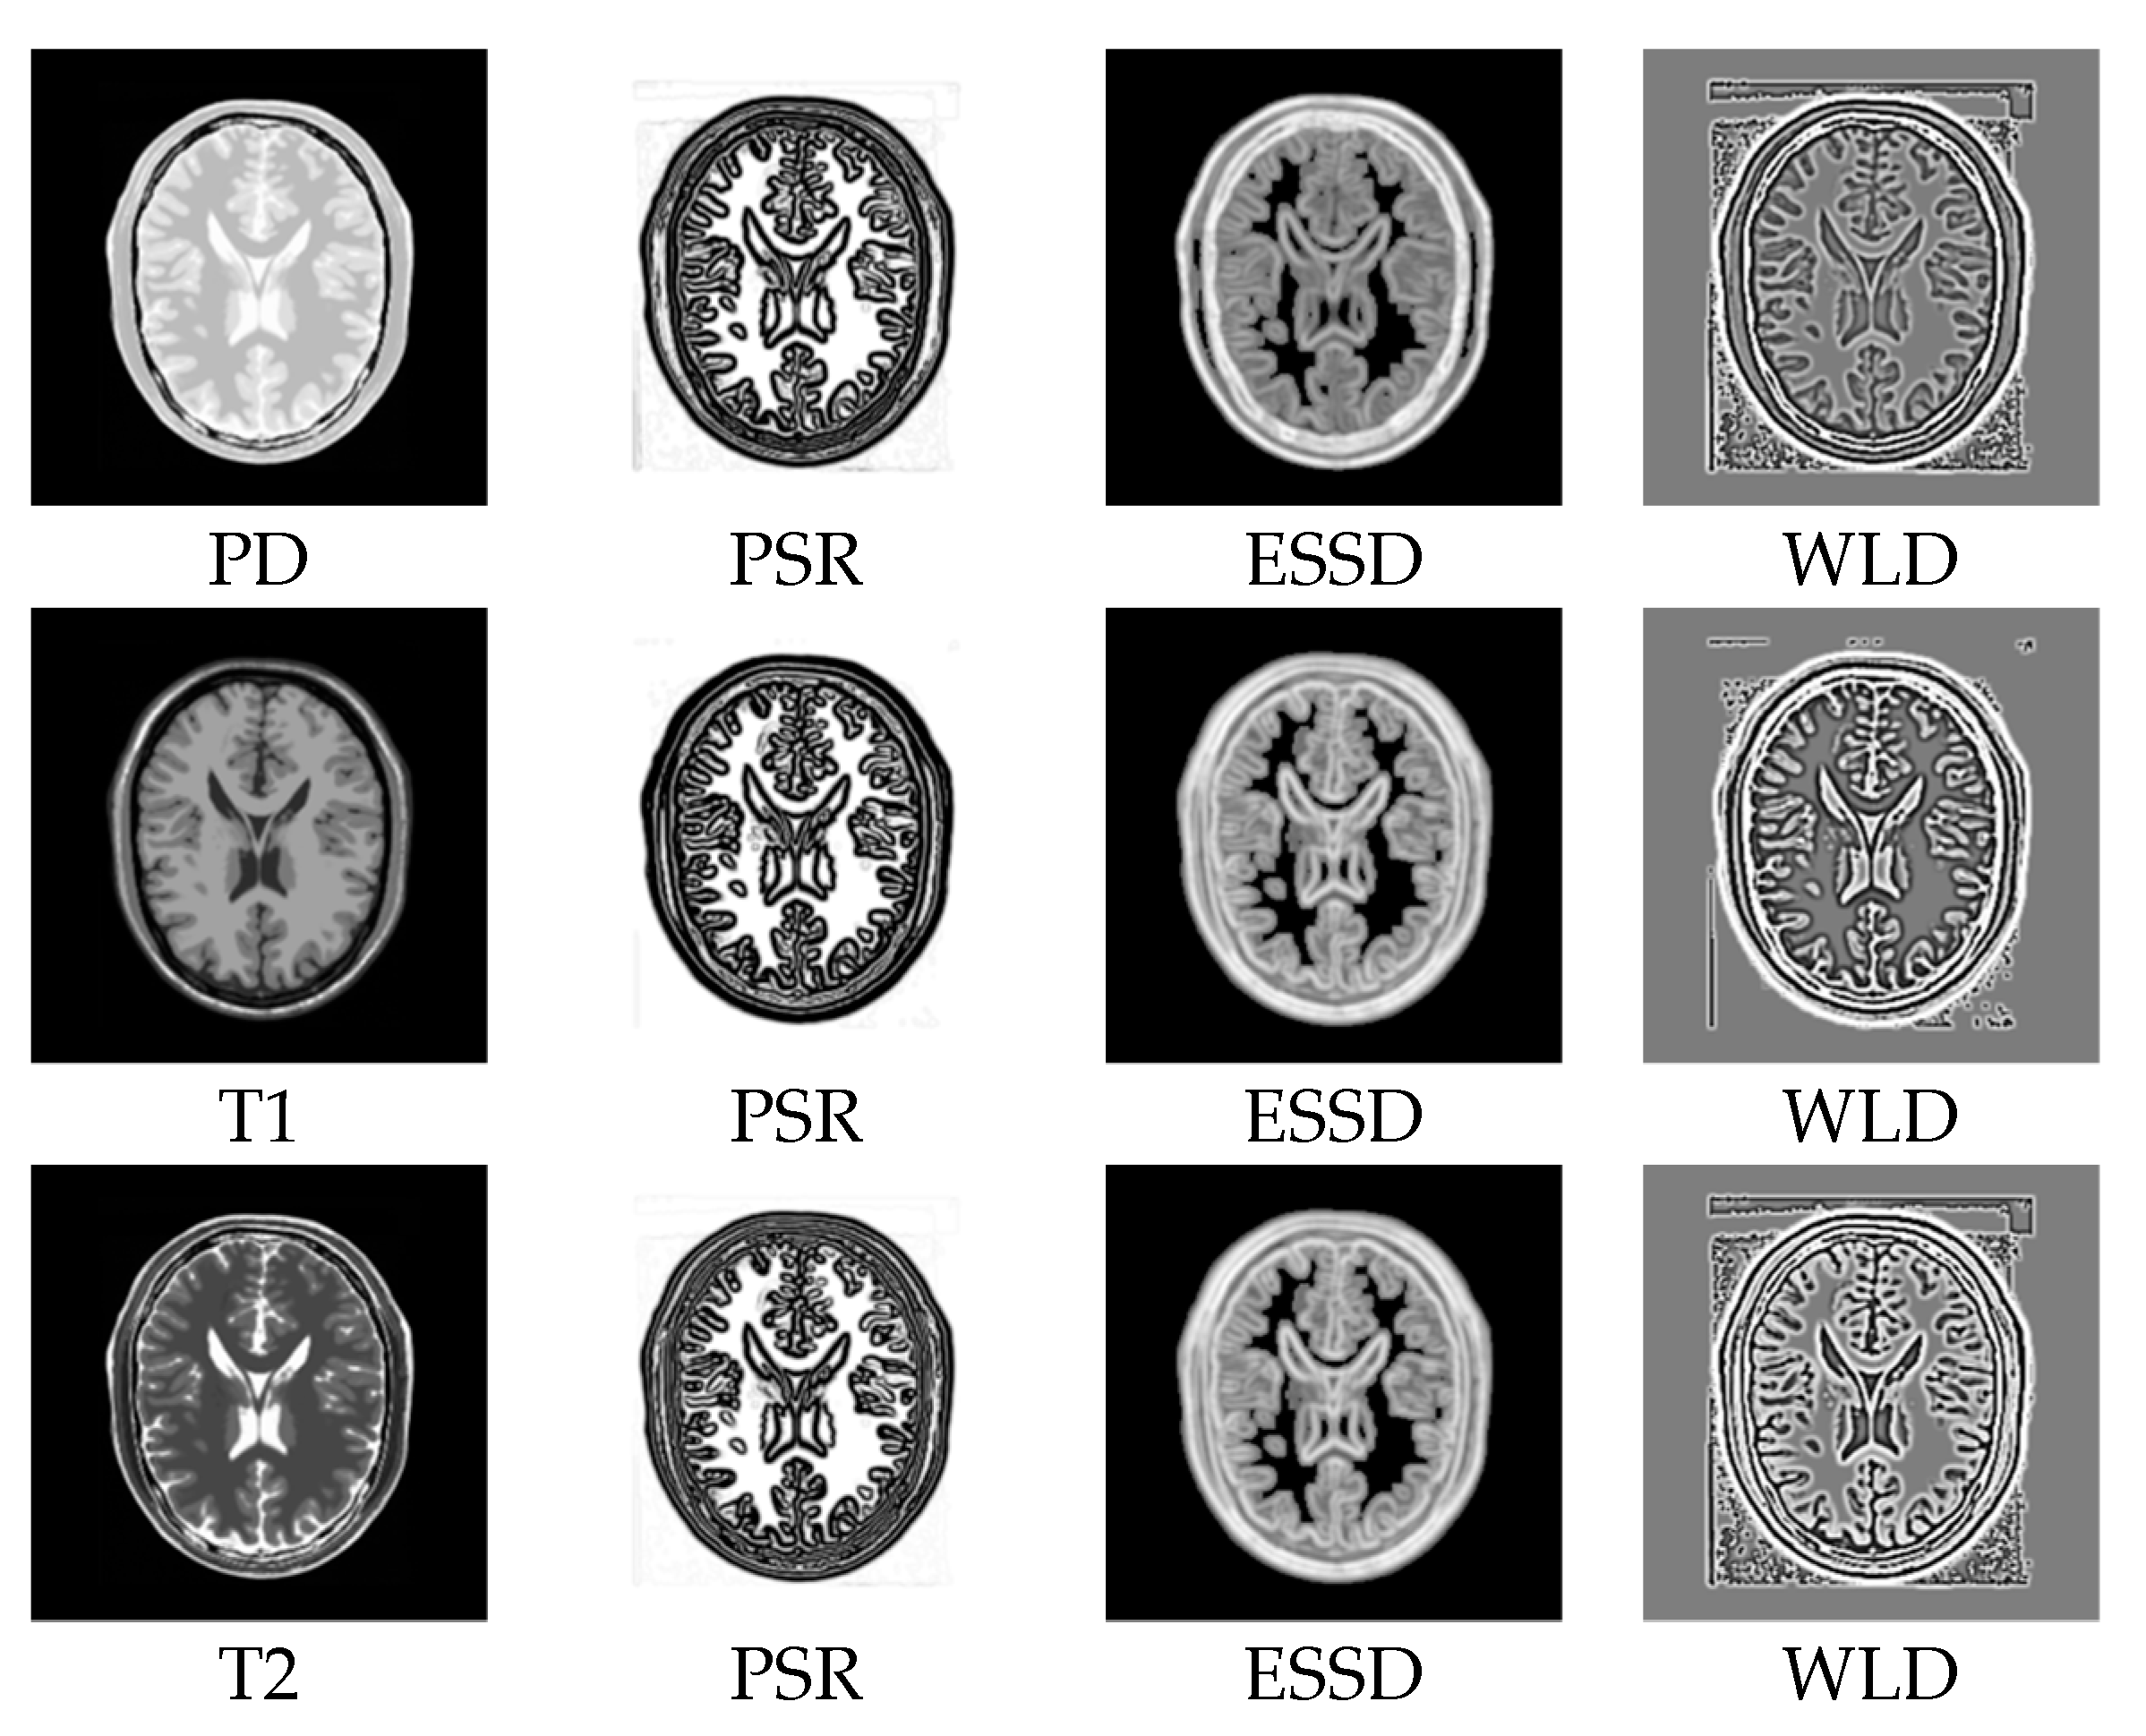

2.2. Structural Representation